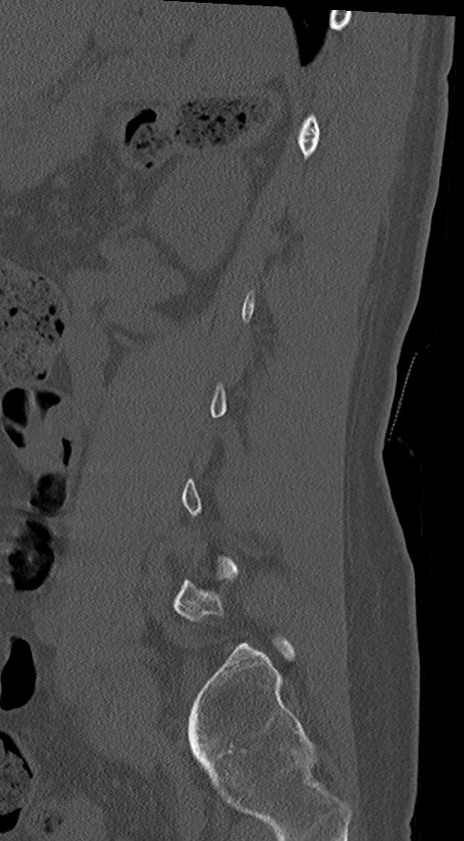

【整形】TIPS症例4 腰椎CT(矢状断像)

腰椎CT